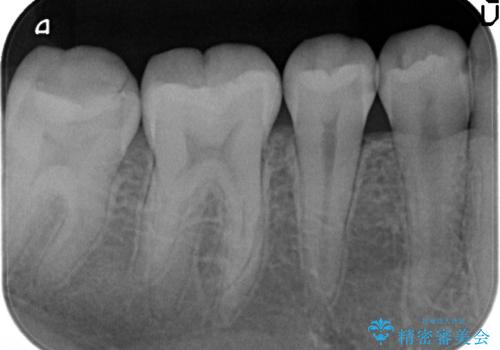

- 右下の4、5番目の歯がしみるといらっしゃった方の症例です。

右下4の遠心及び右下5の近心部が痛むとのことだったので、虫歯除去後、セラミックインレーによる修復を行いました。